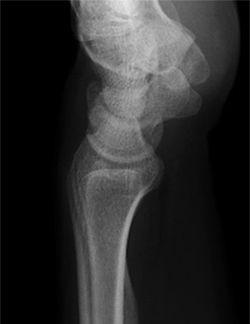

【正常な手関節X線像】

正面像

側面像